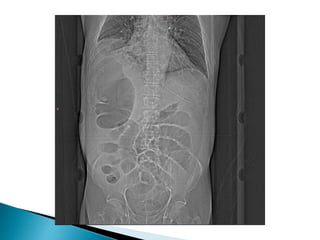

 Diagnosis Abdominal plainfilms usually diagnostic Inverted U-shaped appearance of distended sigmoid loop  Largest and most dilated loops of bowel are seen with volvulus  Loss of haustra  Coffee-bean sign à midline crease corresponding to mesenteric root in a greatly distended sigmoid  Sigmoid volvulus – bowel loop points to RUQ

large, dilated loop of large bowel with an inverted U-shape

with walls between two volvulated loops pointing from LLQ toward RUQ;

same patient with decompressed sigmoid volvulus following insertion of rectal tube